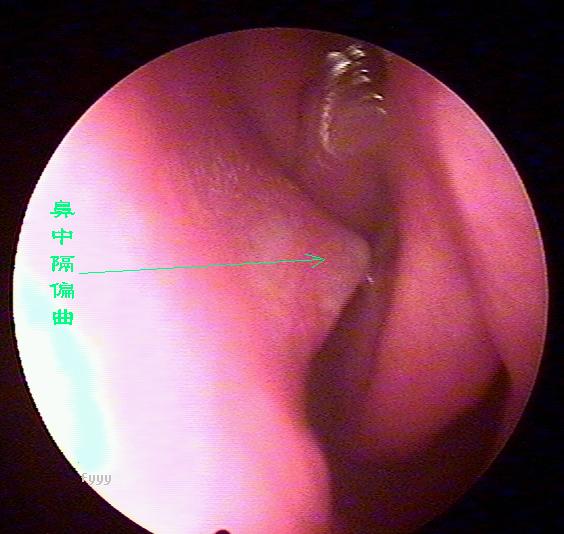

鼻中隔偏曲的症状都有哪些

鼻中隔偏曲的诊断检查

鼻中隔偏曲进行鼻内检查以判断鼻中隔偏曲的类型和程度,注意鉴别鼻中隔粘膜肥厚和是否同时存在鼻内其它疾病,如原发病变—肿瘤、异物或继发病变—鼻窦炎、息肉等。 另一罕见者为鼻中隔梅毒瘤,其质地中亦较硬,但该处粘膜明显充血。